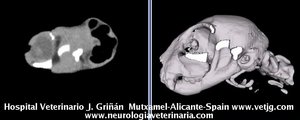

imágenes de TC en el gato | |||||||||||

Mismo paciente: Correspondencias entre el corte sagital y el volumen, ambos reconstruidos a partir de imágenes TC (transversales) |